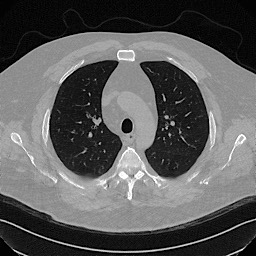

Denoising diffusion probabilistic models (DDPMs) have achieved unprecedented success in computer vision. However, they remain underutilized in medical imaging, a field crucial for disease diagnosis and treatment planning. This is primarily due to the high computational cost associated with (1) the use of large number of time steps (e.g., 1,000) in diffusion processes and (2) the increased dimensionality of medical images, which are often 3D or 4D. Training a diffusion model on medical images typically takes days to weeks, while sampling each image volume takes minutes to hours. To address this challenge, we introduce Fast-DDPM, a simple yet effective approach capable of improving training speed, sampling speed, and generation quality simultaneously. Unlike DDPM, which trains the image denoiser across 1,000 time steps, Fast-DDPM trains and samples using only 10 time steps. The key to our method lies in aligning the training and sampling procedures. We introduced two efficient noise schedulers with 10 time steps: one with uniform time step sampling and another with non-uniform sampling. We evaluated Fast-DDPM across three medical image-to-image generation tasks: multi-image super-resolution, image denoising, and image-to-image translation. Fast-DDPM outperformed DDPM and current state-of-the-art methods based on convolutional networks and generative adversarial networks in all tasks. Additionally, Fast-DDPM reduced training time by a factor of 5 and sampling time by a factor of 100 compared to DDPM. Our code is publicly available at: https://github.com/mirthAI/Fast-DDPM.